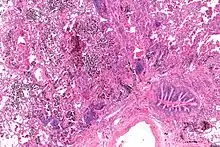

Micrograph showing a pulmonary hemorrhage. H&E stain.